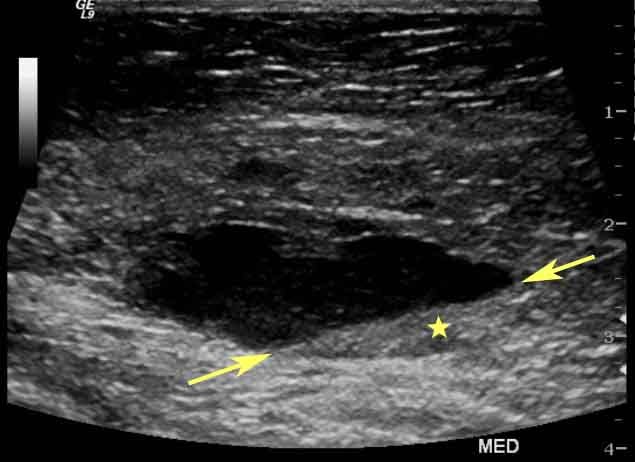

breast ultrasoundEl ultrasonido mamario es uno de los procedimientos diagnósticos más utilizados para examinar las mamas y detectar posibles anormalidades como quistes, tumores o masas. A menudo, las pacientes tienen dudas sobre la naturaleza de este procedimiento, preguntándose si es doloroso o invasivo. Este artículo se centra en aclarar estas inquietudes, proporcionando detalles sobre las sensaciones comunes que se experimentan durante el ultrasonido mamario, comparándolo con otros estudios diagnósticos y ofreciendo consejos para aquellas pacientes preocupadas.

El ultrasonido mamario, también conocido como ecografía mamaria, es un examen no invasivo que utiliza ondas sonoras de alta frecuencia para crear imágenes detalladas de los tejidos internos de las mamas. Esta técnica permite a los médicos identificar quistes, tumores y otras anomalías en los senos. A diferencia de la mamografía, que utiliza radiación, el ultrasonido mamario no implica exposición a rayos X, lo que lo convierte en una opción más segura para ciertos grupos de pacientes, como mujeres jóvenes o embarazadas.